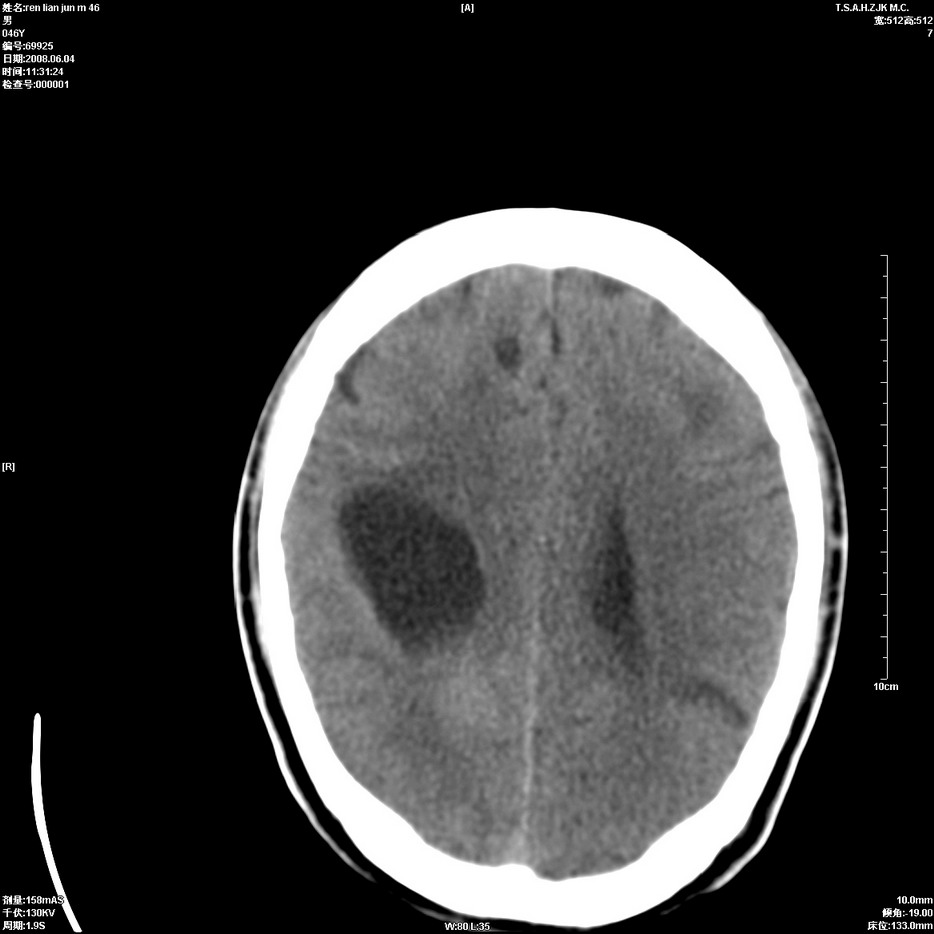

以下是引用qiu999在2008-6-5 17:14:00的发言:[br]考虑右肺中心型肺癌.颅内应做增强检查.

以下是引用形影不离在2008-6-5 19:18:00的发言:[br]右肺中心型肺癌并纵隔及左侧腋窝淋巴结转移,颅内应做增强检查。

以下是引用杀毒软件在2008-6-5 18:33:00的发言:[br]支持考虑右肺中心型肺癌,颅内病变是不是转移,不好说